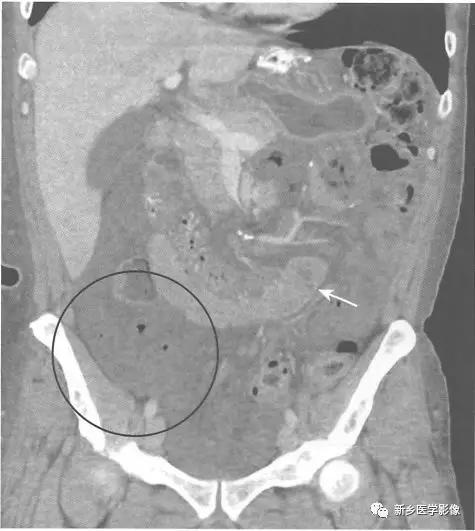

CT可用来确定梗阻原因、评估是否存在腹腔游离气体以及明确相关并发症,如肝脏或淋巴结转移等。

在梗阻部位近端大肠肠腔扩张,在梗阻部位远端肠腔直径恢复正常。

梗阻处通常是结肠癌造成,在CT上表现为软组织肿块,累及大肠的疝也很容易在CT上显示。